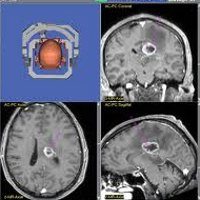

Стереотаксическая биопсия опухолей головного мозга. Диагностическая нейрохирургическая операция проводится для сбора образца опухолевой ткани с целью его детального изучения. Полученные данные о типе неоплазии и степени злокачественности позволяют принять решение о целесообразности хирургического лечения, объеме хирургического вмешательства и методах консервативной терапии (химиотерапия, облучение). Стереотаксическая биопсия выполняется путем создания небольшого отверстия в костях черепа и взятия материала специальной иглой. Нейронавигация или стереотаксическая рамка используется для точного определения местоположения модифицированной мозговой ткани.

В современной неврологии хирургия выполняется в сложных диагностических случаях, когда другие методы обследования (КТ или МРТ) не дают точной информации о патологическом образовании головного мозга и не могут отличить опухолевый процесс от абсцессов мозга, гематом, гранулем или очага демиелинизирования. Кроме того, проводится биопсия для выявления сопутствующего инфекционно-воспалительного процесса в ткани мозга. Стереотаксическая биопсия особенно важна, когда опухоль находится в функциональных и труднодоступных местах. Техника позволяет поддерживать жизненно важные структуры мозга, которые могут быть повреждены в результате обширных хирургических процедур.